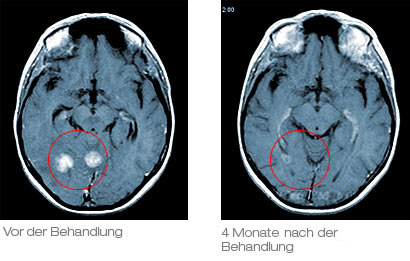

Das linke Bild zeigt MRT-Aufnahmen eines Patienten mit 2 Hirnmetastasen eines Lungenkarzinoms. Beide Tumore wurden in einer 1-stündigen Behandlungssitzung mit dem Cyberknife behandelt. Auf dem rechten Bild zeigt sich die Situation 4 Monate nach der Cyberknife Behandlung. Beide Tumore sind komplett ausgeschaltet, der Patient konnte bereits am Tag nach der Behandlung wieder seiner gewohnten Arbeit nachgehen.